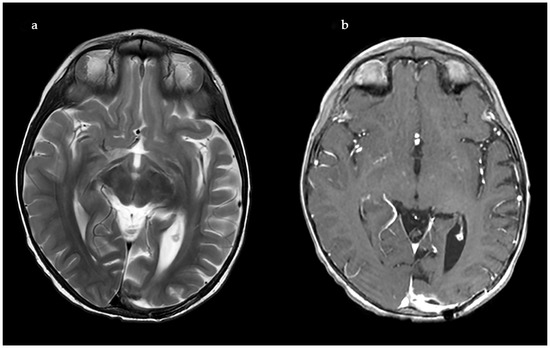

A Rare Case of Rhizomucor pusillus Infection in a 3-Year-Old Child with Acute Lymphoblastic Leukemia, Presenting with Lung and Brain Abscesses—Case Report

Invasive Mucormycosis (IM) is an extremely rare infection with a high mortality rate, caused by a group of fungi classified as Mucorales moulds. Rhizomucor pusillus is a saprophitic, thermophilic, and angioinvasive microorganism that grows and lives at about 45 °C and is usually found in different environmental spaces such as soil, air, water, food, and other organic matter. These features predispose the infection to wide dissemination, especially in immunocompromised patients and most often in children after chemotherapy for hematological malignancies (HMs). Mucormycosis in patients with hematologic malignancies and neutropenia represents between 0.07% and 4.29% of the concomitant diseases. IM can develop into an infection in different sites, but its most common manifestation is pulmonary, followed by rhino-orbital–cerebral and disseminated forms. In recent years, an increased morbidity rate has been associated with the ongoing COVID-19 pandemic, as cited in the literature. There are many publications with COVID-19-associated mucormycosis (CAM) cases. The present treatment protocol includes extensive and radical surgical debridement and systemic antifungal therapy with Liposomal Amphotericin B (L-AmB), Posaconazole, and Isavuconazole, either combined or as monotherapy. Despite these new treatment modalities, the mortality rate remains over 50%. We present a rare case of a 3-year-old child with acute lymphoblastic leukemia (ALL) and systemic Rhizomucor pusillus infection, diagnosed on the occasion of lung and brain abscesses. The patient underwent lung and brain surgery and is recovering well with no further complications. The two-year follow-up period shows no signs of recurrence of the disease. Full article

Show Figures

Figure 1